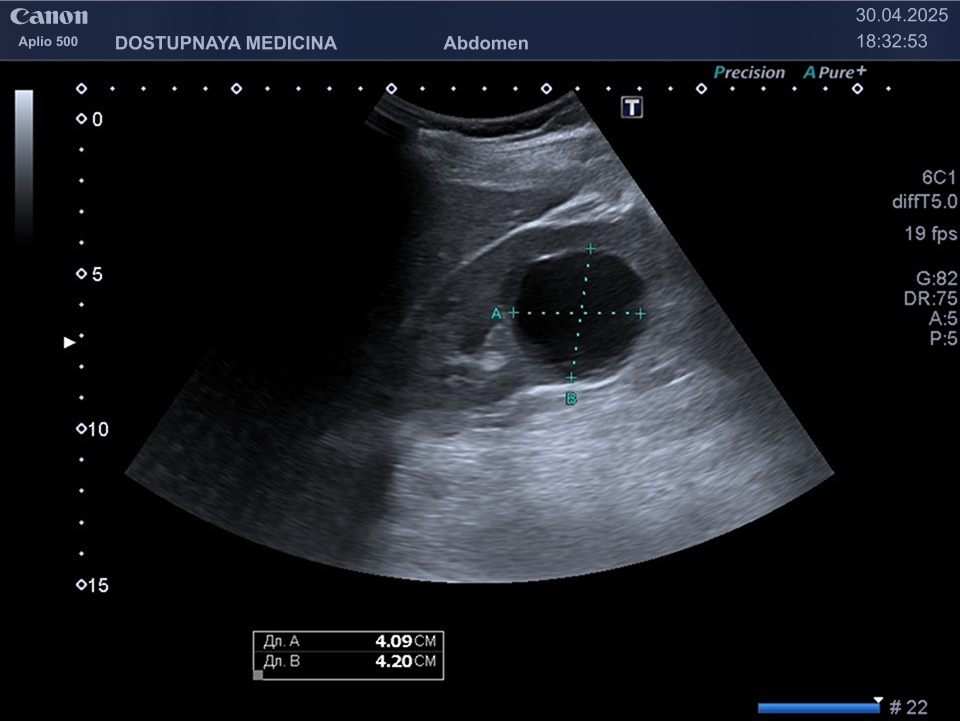

Чаще всего кисты почек протекают бессимптомно и являются случайной находкой во время ультразвукового исследования. При увеличении кисты в размерах может появиться боль в поясничной области в результате раздражения образованием нервных окончаний почки. Большая киста может сдавливать сосуды почек, приводя к нарушению кровотока в органе вплоть до полной гибели органа с развитием почечной недостаточности. Киста, локализованная в почечном синусе, может сдавить лоханку и чашечки почки, что приводит к нарушению оттока мочи вплоть до гидронефротической трансформации почки с полной утратой её функции. Поэтому очень важен периодический контроль размеров кисты не реже 1 раза в 6-12 месяцев.

Кисты небольших размеров (до 3 см), как правило, не требуют никакого лечения, необходимо лишь контролировать размеры и количество кист не реже 1 раза в 6-12 месяцев. Кисты от 3 до 5 см можно пунктировать и дренировать под контролем УЗИ с последующим введением в них склерозирующего препарата. Более крупные кисты (больше 5 см), как правило, иссекают лапароскопически. Медикаментозного лечения кист на данный момент не существует.

Существует классификация кист Bosniak по степени онкологической опасности:

- Bosniak 2 – киста с перегородками и толщиной стенки 3мм или простая киста больше 3 см, требует наблюдение 1 раз в 2 месяца